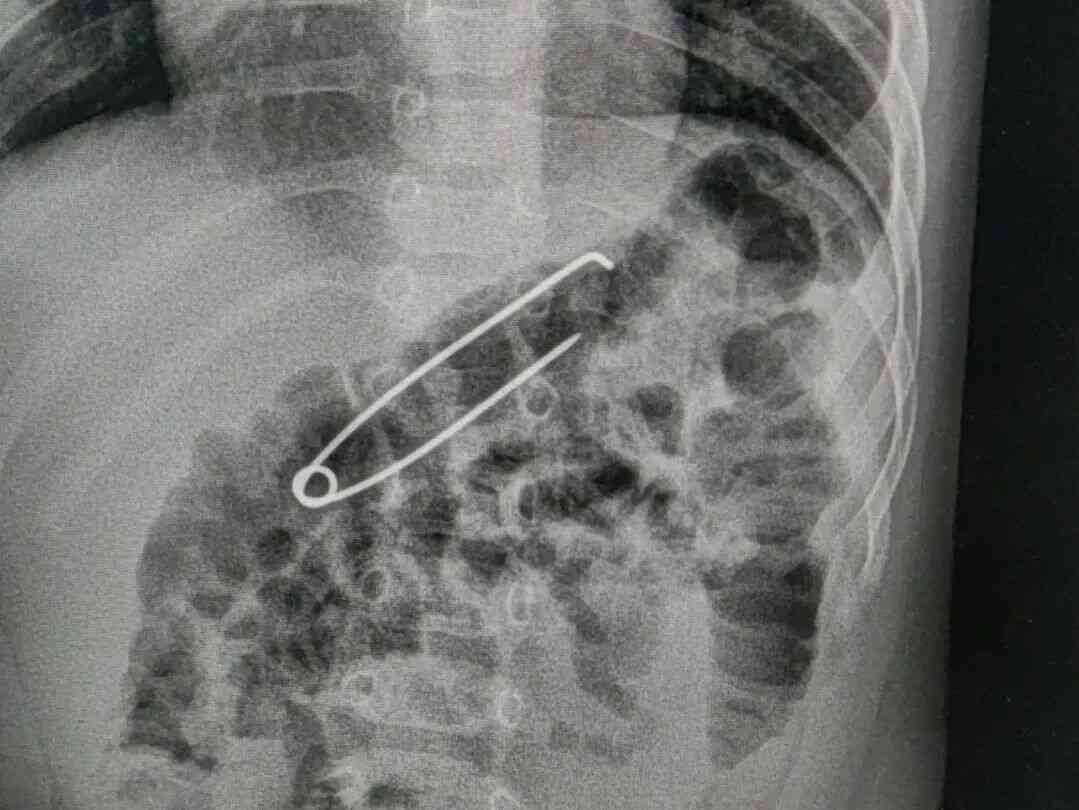

2026年3月4日,北海一名6个月大的男宝宝,不慎误吞一枚长约5厘米的金属扣针,情况危急。

接诊医生立即完善拍片检查,确认异物存在后,迅速组织消化内科、小儿外科等多学科会诊。考虑患儿月龄小、扣针体积较大,为最大限度保障手术安全与术后复苏效果,医院第一时间将患儿收入儿科住院治疗。

患儿收入儿科病房后,值班医师包少萍副主任医师和主治医师伍际玉等医护人员立即为其完善CT检查,明确扣针位于胃内,同时,联系消化内科、麻醉科和手术室做好急诊手术准备。

取出的扣针长5厘米宽1.2厘米。“幸好扣针是扣着的,如果针尖打开,后果不堪设想。”谭丽医生说。